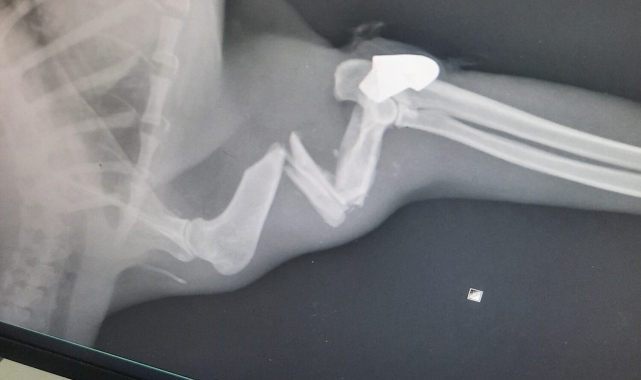

Veterinerde yapılan müdahale sonrası şaşkınlıklarının daha da arttığını belirten Seda Özkaya, "1,5-2 aydır kayıptı. Artık 'Herhalde öldü' diye kabullenmiştik. İki gün önce diğer kedime bakarken bir baktım bu geldi. Çok sevindim ama koluna basamıyordu. Kırık zannıyla buraya geldik ancak röntgende kurşun çıktı" ifadelerini kullandı.

Tedavinin başarılı geçtiğini ve kedisine artık evinin çatısında özel bir yer hazırladığını söyleyen Özkaya, "Kemiği çıktı sandık ama kurşun isabet etmiş. Ameliyatı yapıldı. Çok şükür sağlığına kavuştu. 15 gün sonra kontrole getireceğiz" dedi.

Konuyla ilgili bilgi veren Zonguldak Belediyesi Veteriner Hizmetleri Müdürü Rıza Akçay, olayın net bir ateşli silah yaralanması olduğunu doğruladı. Akçay, "Çektiğimiz röntgenlerde durum belliydi. Mermi çekirdeği de üzerindeydi, bu yüzden yorgun mermi olduğunu teyit ettik. Gerekli cerrahi müdahaleyi yaparak ameliyatını gerçekleştirdik. Operasyon başarılı geçti. İnşallah en kısa zamanda eski sağlığına kavuşacak" şeklinde konuştu.